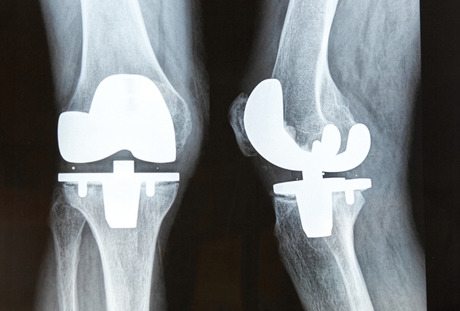

Biðlistar eftir völdum aðgerðum eru ýmis jafnlangir eða lengri en í fyrra skv. nýju yfirliti Landlæknis. Bið eftir skurðaðgerð á augasteini lengist enn og eru ríflega tvö þúsund manns á biðlista. Hafa þeir ekki verið fleiri frá því að reglubundin innköllun Embættis landlæknis hófst árið 2007 og nemur aukningin 42% vmiðað við stöðuna í fyrra. Einstaklingum sem bíða eftir gerviliðaaðgerð á mjöðm hefur t.d fjölgað sem og þeim sem bíða eftir gerviliðaaðgerð a hné. Er áætluður biðtími síðari hópsins 78 vikur. Einungis hefur fækkað hvað hjarta og/eða kransæðamyndatöku snertir.

Á vef Embættis landlæknis kemur fram að embættið birti reglulega upplýsingar um biðlista eftir völdum skurðaðgerðum. Á heildina litið er um fjölgun að ræða eða óbreytt ástand á biðlistum þeirra völdu skurðaðgerða sem hér um ræðir. Einstaklingum sem beðið hafa lengur en þrjá mánuði eftir gerviliðaaðgerð á mjöðm hefur fjölgað nokkuð, eða um rúm 10% frá því í júní á þessu ári. Nú eru 247 einstaklingar á biðlistanum en voru 224 í júní.

Sama á við um þá sem eru á biðlista eftir gerviliðaaðgerð á hné, þeim hefur fjölgað um 14,5% á sama tíma. Nú bíða 483 lengur en þrjá mánuði eftir aðgerð og er áætlaður biðtími á Landspítala orðinn 78 vikur. Áætluð bið eftir gerviliðaaðgerð á mjöðm er hins vegar 29 vikur á Landspítala. Á Heilbrigðisstofnun Vesturlands er áætluð bið eftir báðum tegundum aðgerða 48–60 vikur.